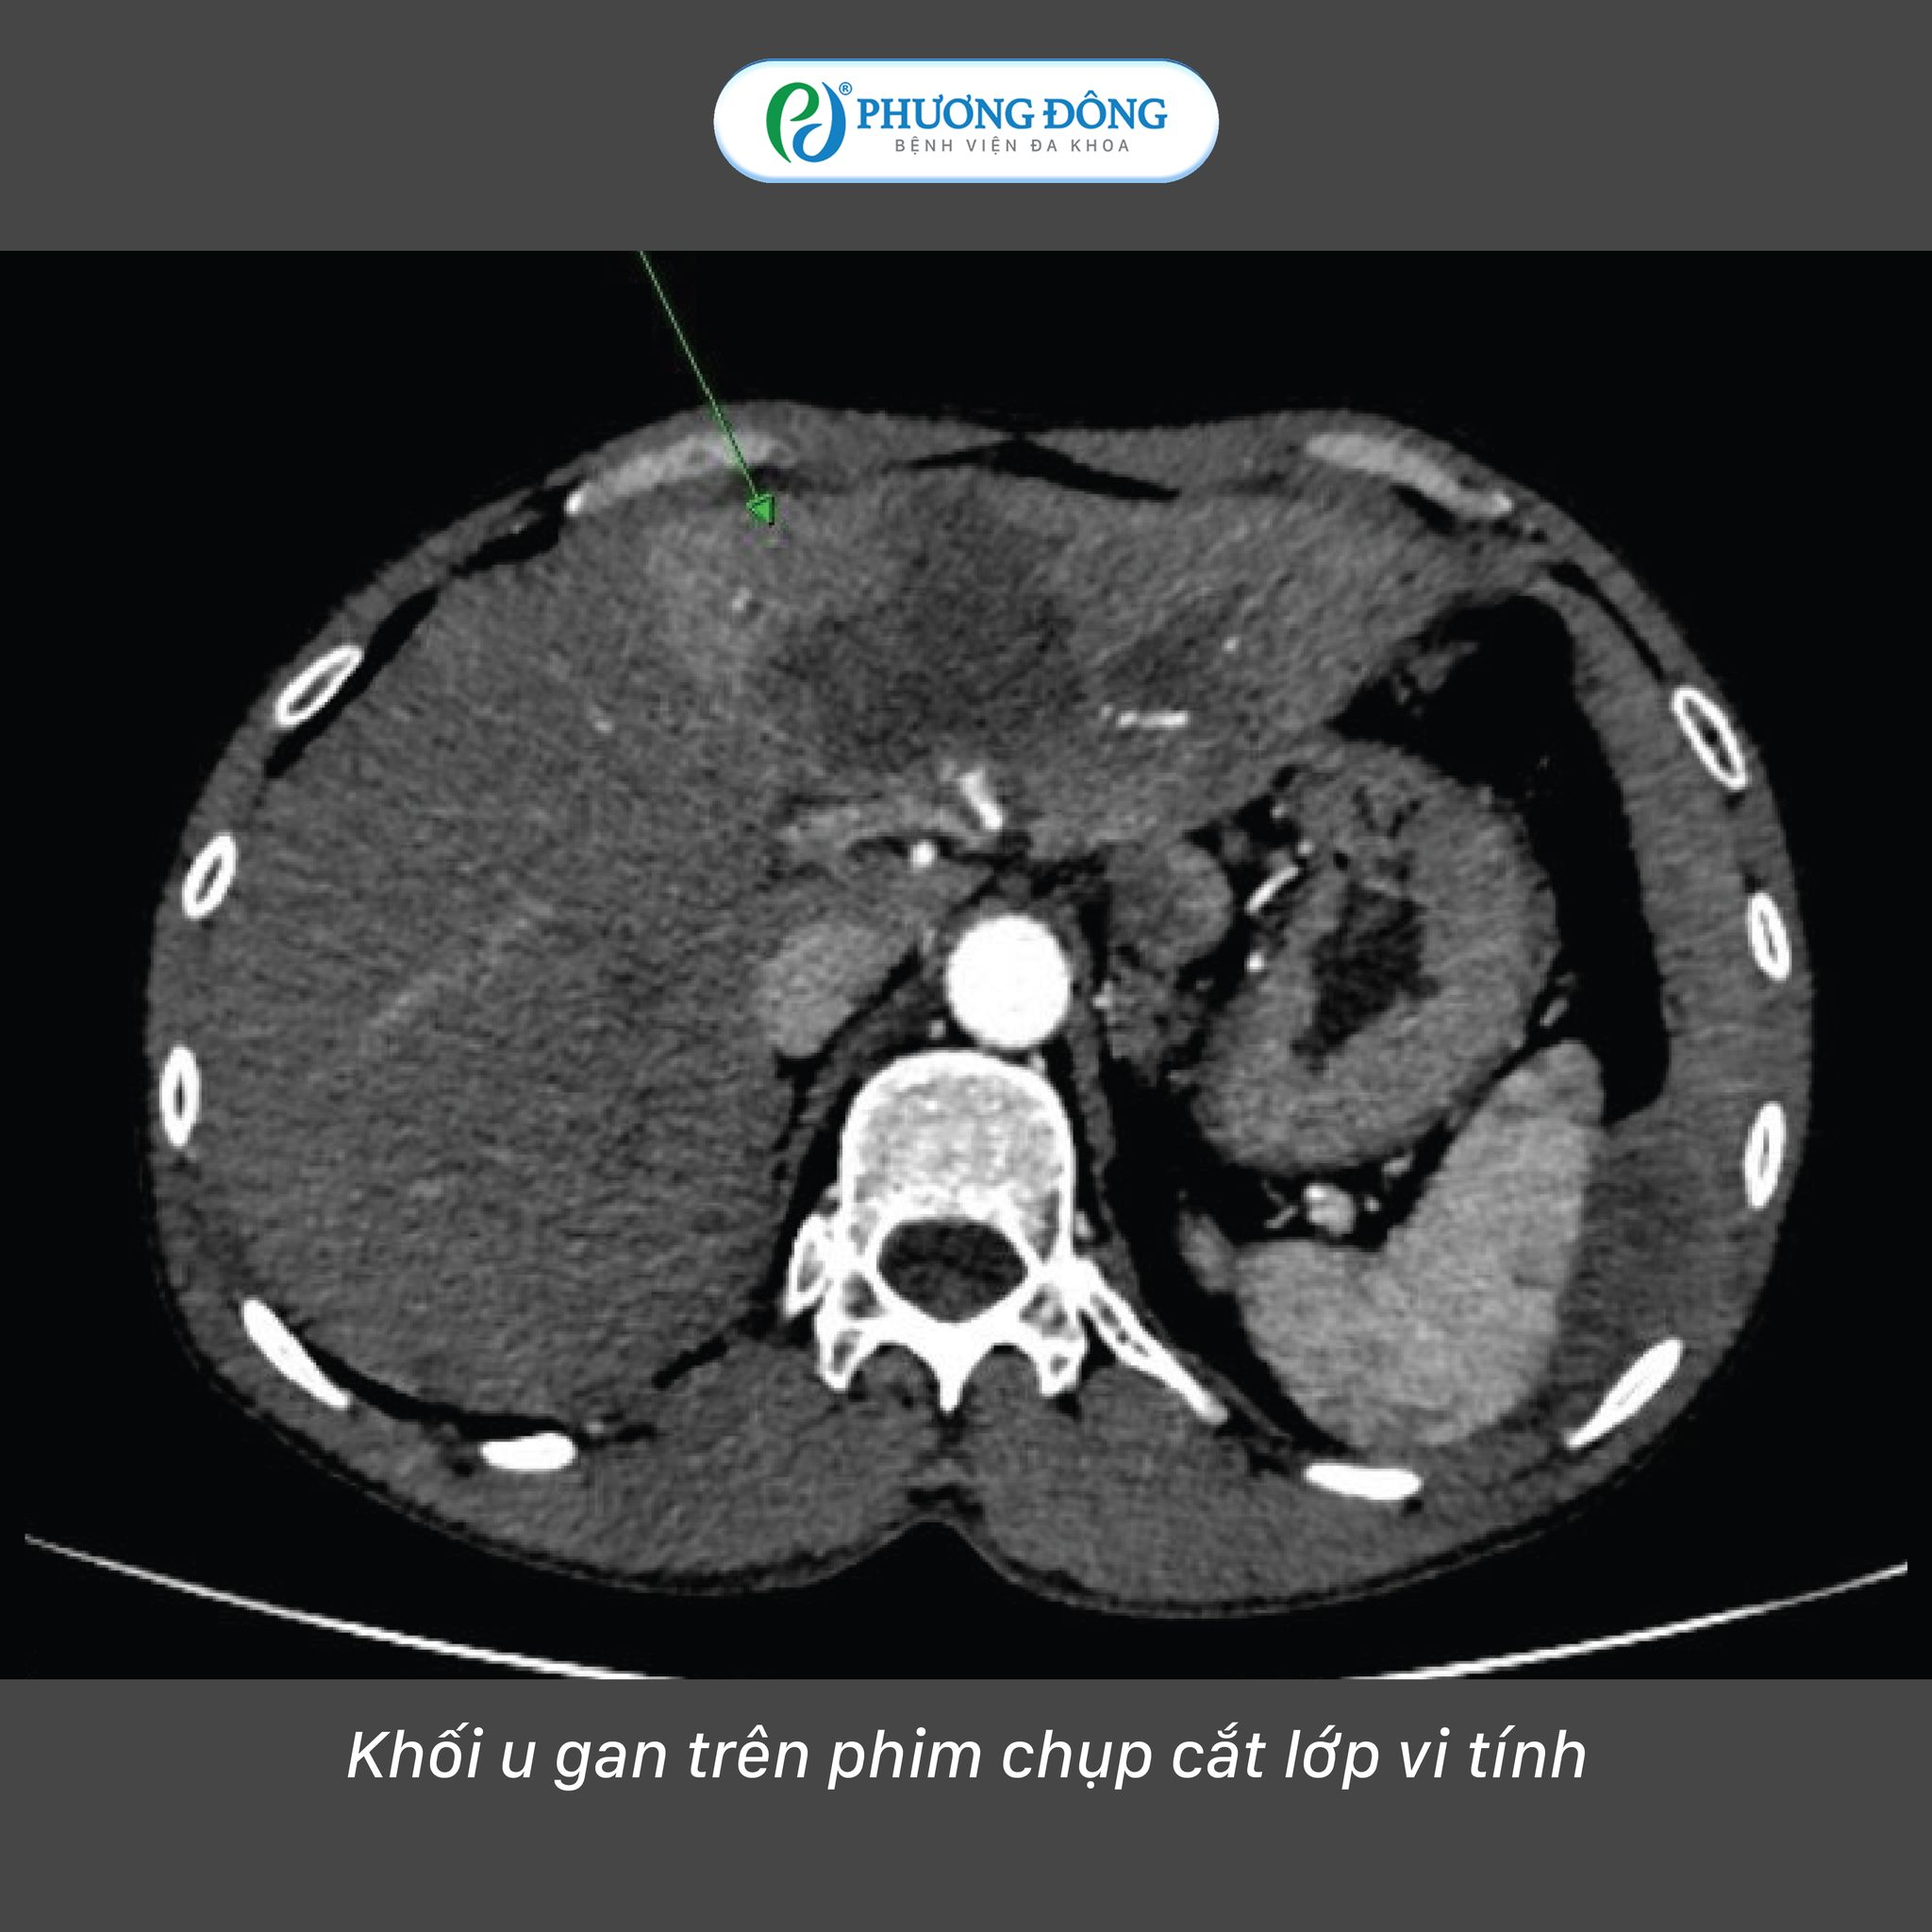

Dù có tiền sử mắc bệnh, bệnh nhân đã tự ý ngừng thuốc trong thời gian dài, khiến khối u tiến triển âm thầm. Khi nhập viện tại BVĐK Phương Đông với biểu hiện mệt mỏi và đau tức hạ sườn, bác sĩ xác định bệnh nhân đã mắc ung thư biểu mô tế bào gan (HCC) với kích thước u lớn, kèm theo chỉ số AFP tăng cao, tải lượng HBV tăng mạnh và chức năng gan suy giảm đáng kể.

Trước tình trạng đó, các chuyên gia tại Trung tâm Chẩn đoán hình ảnh & Điện quang can thiệp Quốc tế Phương Đông đã lựa chọn hướng tiếp cận bằng kỹ thuật nút mạch hóa chất (TACE) - phương pháp can thiệp chuyên sâu cho phép tác động trực tiếp vào khối u thông qua hệ thống mạch máu nuôi u.